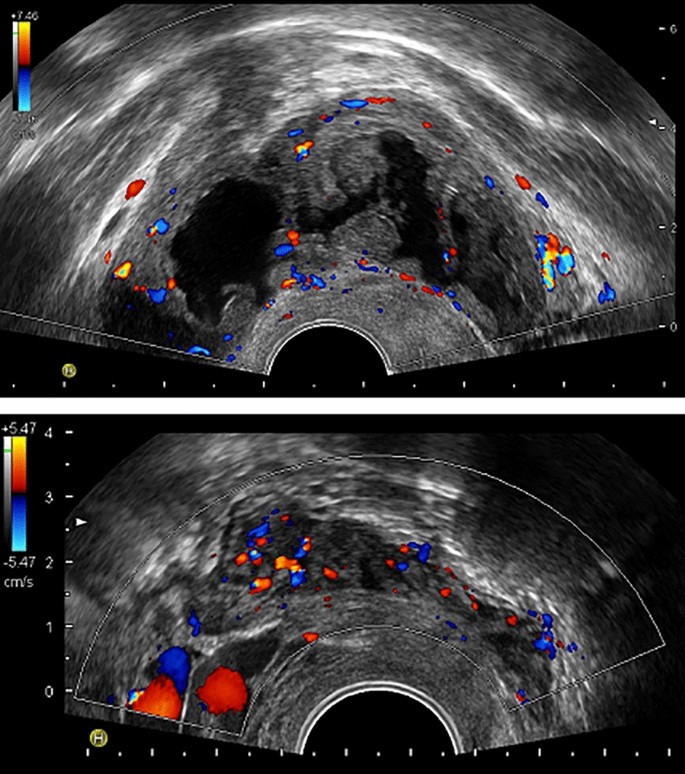

When comparing the mean diameter of the endometrioma between basal and 11–13 weeks’ assessments, no significant difference emerged (25 ± 10 vs 24 ± 15 mm, respectively, p = 0.63). Seven endometriomas in six women developed vascularized papillary projections at the 11–13 weeks’ ultrasound and were deemed decidualized (16%, 95% CI 8–29%). Figure 1 illustrates one of these cases. Signs of decidualization could not be observed at 6–7 weeks’ gestation assessment in any of these seven cases. Three decidualized endometriomas had multiple (three to four) papillary projections and a significant growth of the cyst (increase in diameter of more than 50%). The remaining four had a single vascularized papillary projection and a grossly stable cystic dimension. Among the eight women with bilateral endometriomas, six had no decidualization, one had unilateral decidualization and one had bilateral decidualization. The woman included twice carried endometriomas in both pregnancies and never showed signs of decidualization. Decidualization exclusively occurred in women who had fresh embryo transfer (6/28) whereas it was never observed among those who had frozen embryo transfer (0/12). However, the difference was not statistically significant (Fisher Exact test, p = 0.15). The six women showing decidualization were treated with a GnRH antagonist protocol in 4 cases, a long protocol in 1 case, and a flare-up protocol in 1 case.

Decidualization of ovarian endometriomas and deep peritoneal nodules. In the upper panel, a decidualized endometrioma at 12 weeks’ gestation is shown (Case 6 left, see Table 3). Multiple vascularized papillary vegetations can be observed. Their color score was quoted as 2. In the lower panel, a retrocervical endometriotic nodule at 23 weeks’ gestation is represented (Case 15, see Table 4). The mean diameter of the lesion increased from basal evaluation to 23 weeks’ gestation from 25 to 29 mm. Doppler evaluation showed a color score of 3 (at baseline it was 1).

Four of the 15 DIE nodules could not be identified at the 11–13 weeks’ ultrasound as well as in subsequent scans in pregnancy. One of these four cases occurred in the patient who had bilateral decidualized endometriomas. However, in this case, we cannot exclude that we were just unable to distinguish the DIE nodule because it was in close contact with the two enlarged kissing ovaries carrying the decidualized endometriomas. To note, in this case, the DIE nodule could be easily identified at post-partum assessment, when decidualization of the endometriomas regressed completely. In contrast, in the other three cases that could not be identified in pregnancy, the DIE nodule could not be detected in the post-partum. The analyses were therefore made for the 11 nodules that could be identified at both the basal and the 11–13 weeks’ ultrasound scans. Findings are detailed in Table 4. A significant increase is size emerged: the mean diameter grew from 16 ± 4 to 20 ± 6 mm (p = 0.001). At the 11–13 weeks’ ultrasound, five nodules (45%) showed an increase in blood flow (color score changed from 1 to 2 in four nodules and from 1 to 3 in one nodule). One of these cases is illustrated in Fig. 1. As opposed to what described for endometriomas, we observed changes also after the 11–13 weeks’ assessment. An increase in color score later in pregnancy was documented in three additional nodules (27%). DIE lesions could not be identified in two out of the nine women (22%) who performed the post-partum evaluation. When exclusively consider DIE lesions that were detected both before and after pregnancy (n = 7), no modification in size emerged, the median [IQR] diameter before and after pregnancy being 15 [13–19] and 18 [12–24] mm, respectively (p = 0.35). The mixed model analysis aimed at capturing a general impact of pregnancy on the dimension of the DIE lesion did not detect a statistically significant effect (p = 0.10).